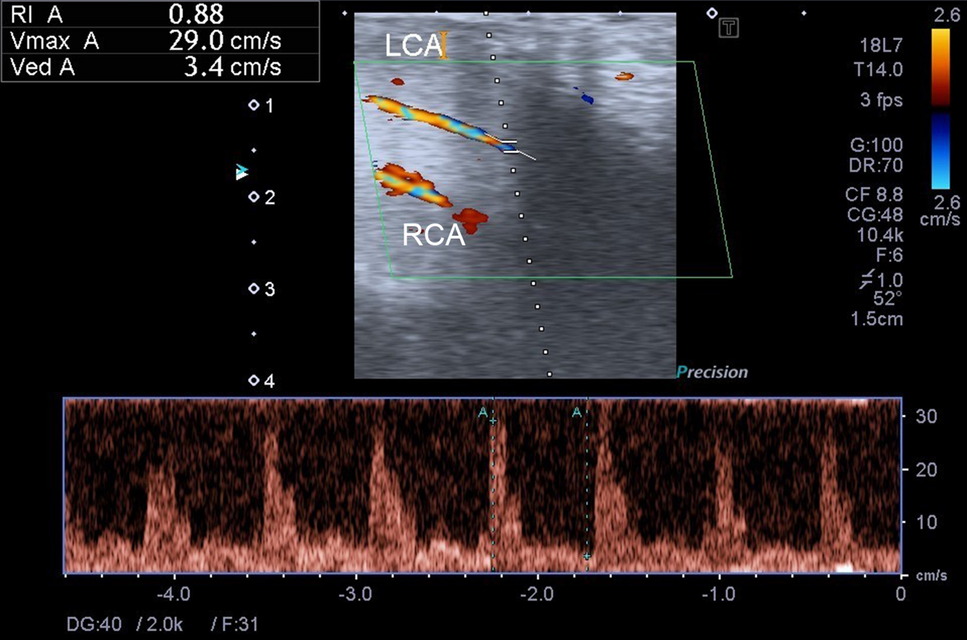

Figure 2

An example of dynamic duplex sonography of the penis. Both LCA and RCA are shown in this sonography. The hemodynamic parameters of the LCA are measured. The PSV (shown as Vmax A) is 29.0 cm/s, the EDV (shown as Ved A) is 3.4 cm/s, and the RI (shown as RI A) is 0.88. EDV: end-diastolic velocity, LCA: left cavernous artery, PSV: peak systolic velocity, RCA: right cavernous artery, RI: resistance index.